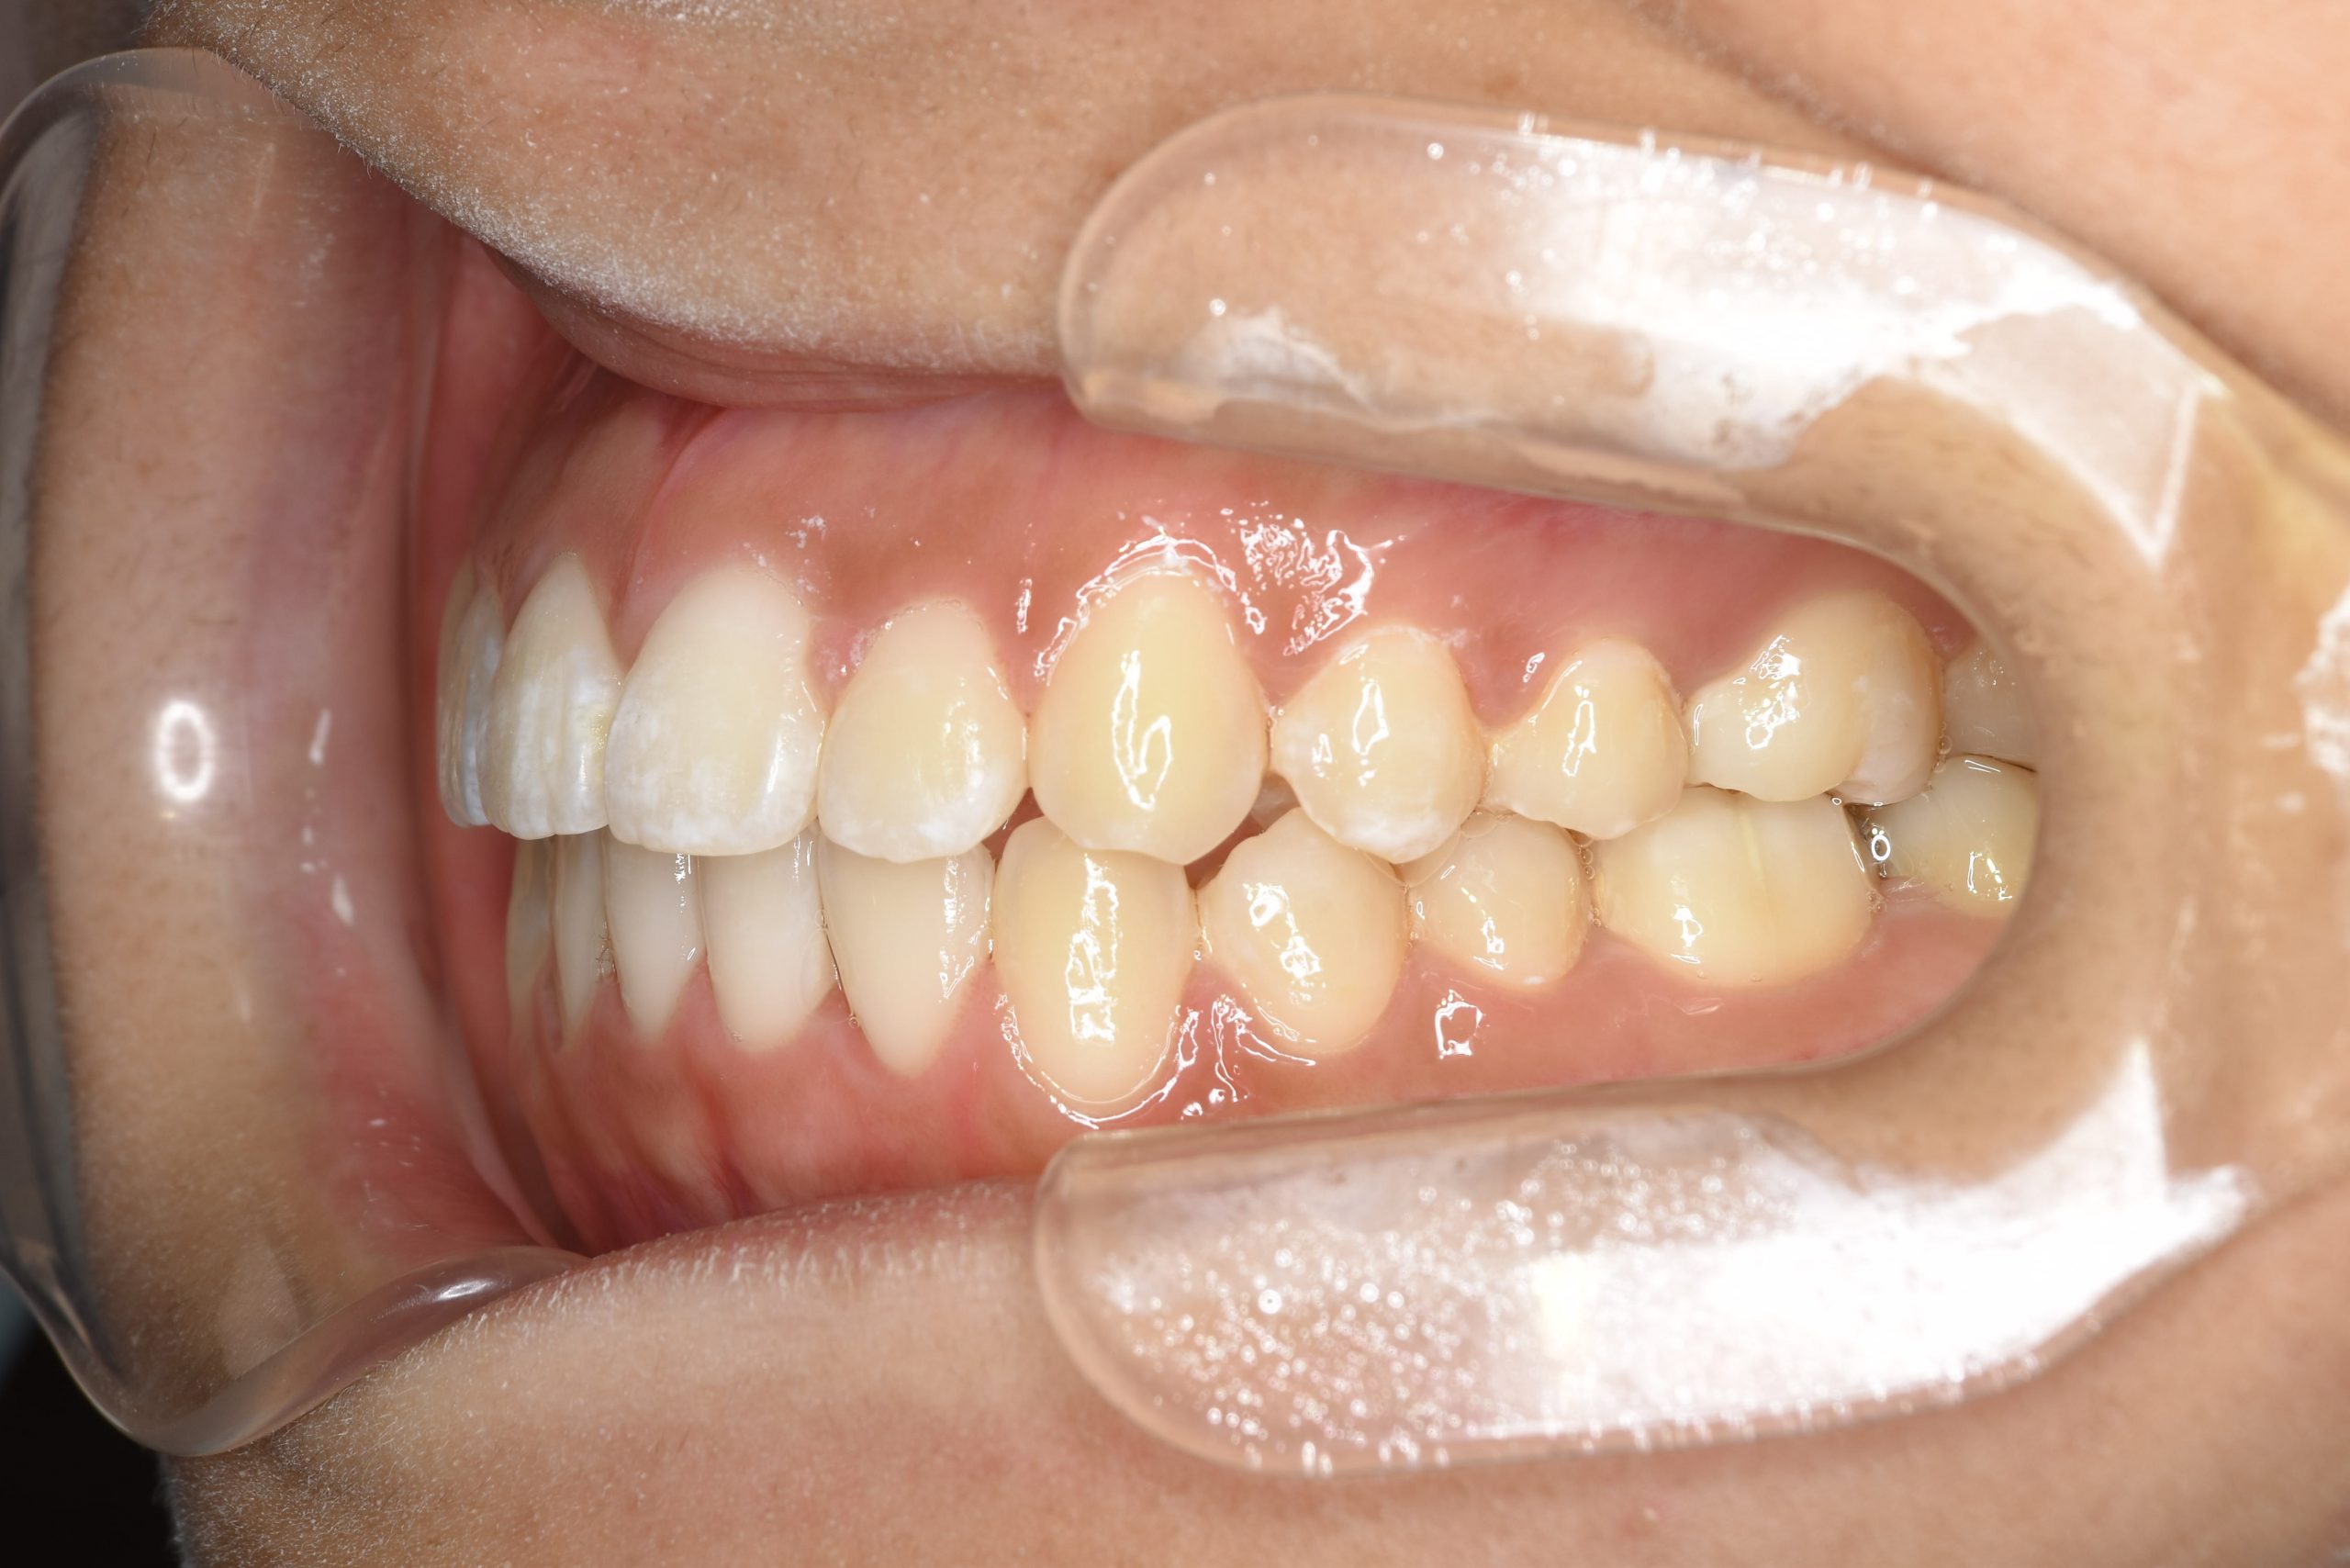

ビフォー

全顎ワイヤー矯正 症例_839